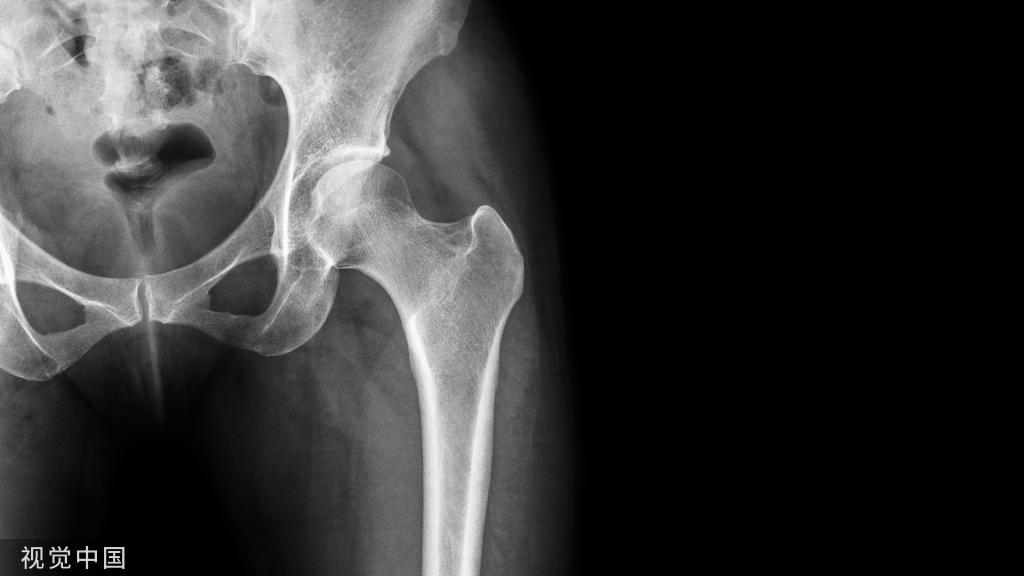

从长骨干取除断裂的髓内钉仍然是一个棘手的问题。本文介绍一种方法,该方法在技术上比文献中描述的其他方法要求低。此方法类似于钓鱼,这是一种通过鱼钩钓鱼的方法。在这种方法中,断裂的钉子在透视引导下钩住,并通过由不锈钢丝制成的钉钩以逆行方式取回。它无创地去除断裂的钉子,需要进一步暴露。1.首先钩子有一个宽阔的嘴,一个窄的弯曲(图A,B)。